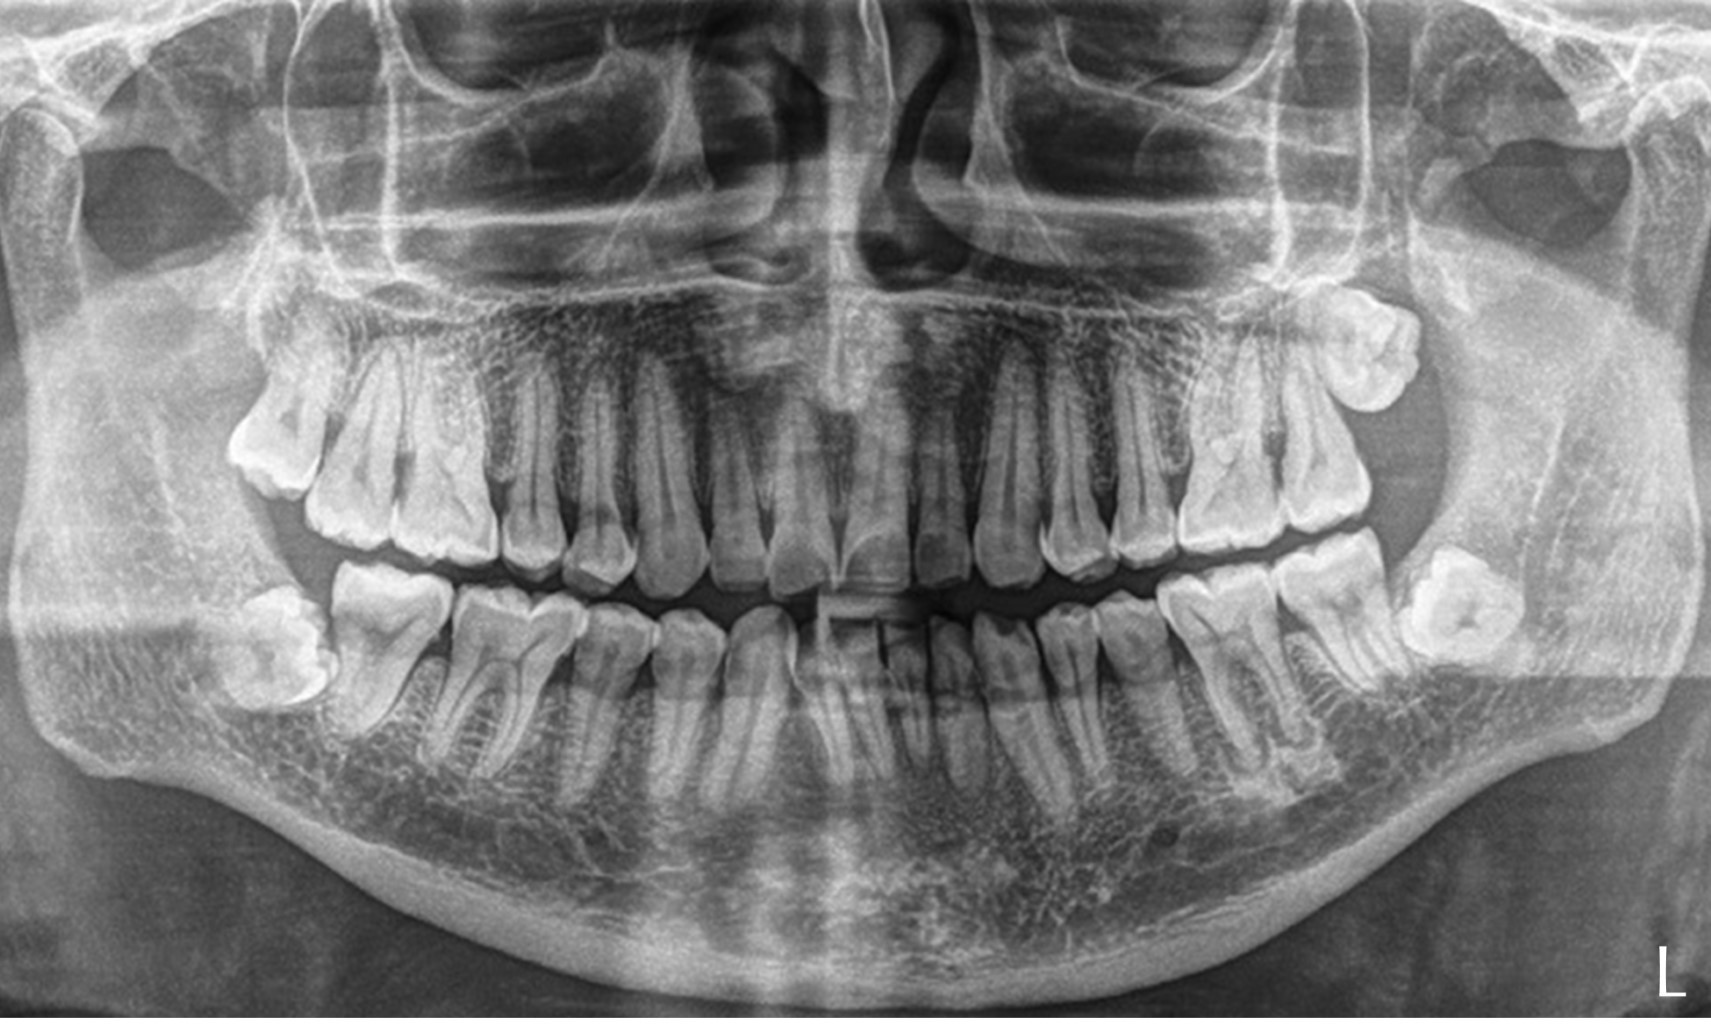

Se solicita ortopantomografía, donde se observa destrucción ósea (Figura 2).